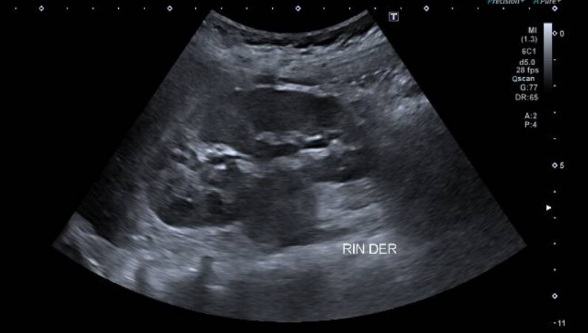

3. ECOGRAFÍA ABDOMINAL

Ecografía abdominal: Voluminosa masa sólida heterogénea, con áreas quísticas, que

se extiende desde el hipocondrio izquierdo hasta fosa ilíaca izquierda. Impresiona de

origen renal. Presenta vascularización periférica al examen Doppler color. En hilio renal

derecho se observa imagen de similares características y de menor tamaño.